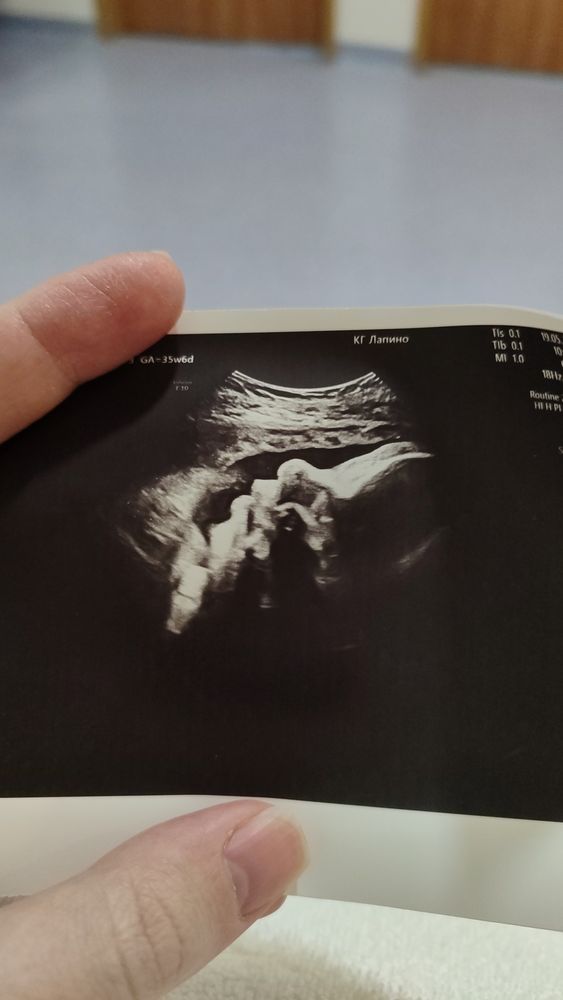

Посмеялась с того, что в прошлом посте написала про последнее УЗИ перед родами, ибо на следующий же день я уехала в роддом, где мне ещё дважды делали УЗИ, и вчера повторяли - следили за кровотоками. Уехала я из-за ужасно низкого давления, боли в груди и ощущением, будто сердце останавливается. Давление было 86/56 при пульсе ниже 60, я такого у себя никогда не видела. В приёмном как-то наметили тоже 80/50, хотя там я уже чувствовала себя нормально, но всё равно положили на ночь на ктг. Утром отпустили, дали с собой домашний ктг, теперь пишу по 2 раза в день. Вроде больше такого не повторялось, и слава богу. Кровотоки вроде норм, но на границе. КТГ пишется хорошее, один раз только было сомнительное.

Зато получила за эту неделю много фоток своей булки. Скоро встретимся, моя маленькая🥰